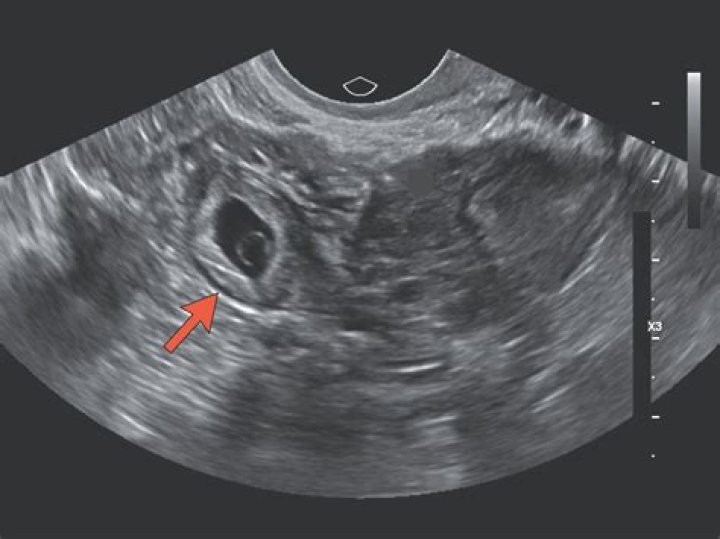

An ectopic pregnancy is usually diagnosed by carrying out a transvaginal ultrasound scan.

An ectopic pregnancy can be suspected if the transvaginal ultrasound examination does not detect an intrauterine gestational sac when the β-hCG level is higher than 1,500 mIU per mL.

An intra-uterine pregnancy can usually be seen by 5-6 weeks gestation or when the HCG level is more than 1000 IU/l. In 95% of ectopic pregnancy cases, a good transvaginal ultrasound examination can actually image the ectopic pregnancy in the Fallopian tube.